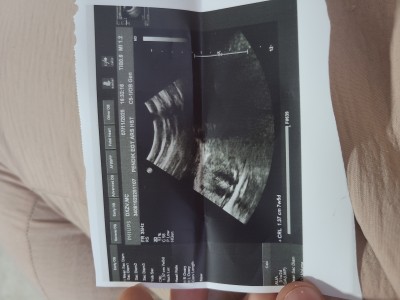

7+5 haftalık hamileyim. Doktor bugun muayene ederken kist var dedi 4 cm

. Sorun olur mu merak ediyorum.  Bi dahaki ay gittiğimde tekrar baktıracağım . Ama aklımda şüphem kaldı

Gebelik haftası 7+5